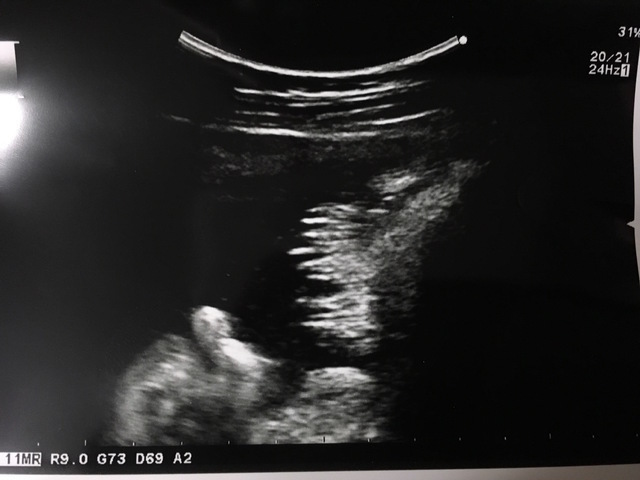

37週3日(37w3d・男の子)|凛句 さん(24歳)

エコー写真撮影時のエピソード:

今年の3月に生まれた長男は、エコー写真を撮影する時、たびたび顔を手で隠して見せてくれない子でした。

この写真を撮った日もお医者さんはなんとか顔が見えるようにと、様々な角度からお腹にエコーを当てて画面に映し出してくれましたが、結局見せてくれず......。

「お顔の写真は撮らせてくれないみたいだから、今日はこの襟足の写真で勘弁してあげてね!」とお医者さんが撮ってくれたのがこのエコー写真です。

「襟足のエコー写真なんて聞いたことない。よっぽど恥ずかしがり屋さんなんだね!」と主人と大笑いしました!子どもがもう少し大きくなったら、この話をしてあげたいなと思っています。